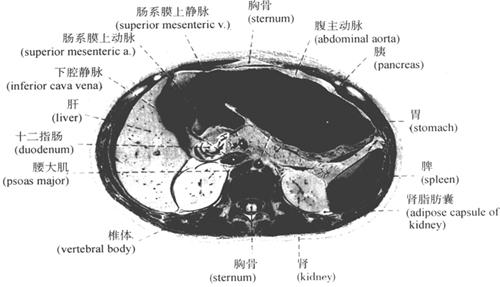

腹膜的配布虽然复杂多样,但在熟悉腹部脏器位置的基础上,按腹部正中矢状切面、横切面(图9-50、图9-51、图9-52)进行观察,还是有规律可循的。腹部壁层的分部以及包被脏器概况泾渭分明,也较易理解壁层腹膜过渡至脏层腹膜或脏层腹膜移行至器官所形成多种结构,如系膜(mesenterium)、网膜(omentum)、韧带(ligament)、皱襞(fold)、陷窝(excavatio)、间隙(space)等。

图9-51 腹膜腔经网膜孔横切面

图9-52 腹膜腔经下腹部横切面